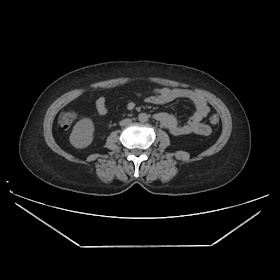

A CT abdomen revealed a left adrenal cortical tumor.

Clinician advised against surgery because she was not in pain. Her TSH is normal. A CT abdomen revealed a left adrenal cortical tumor. Diagnosis of pri. aldosteronism was made. Patient is hypertensive since 1995 since her second childbirth. Now BP is normal with medication. She is nondiabetic. Pt. advised to report her Ca2+ and K+ lvl. monthly. Pt. acq. the habit of eating paan (beetle leaf) from her mother in 2011 when she came to stay with her. Used to eat 3-4 paans a day. Stopped in 2013 after Dr. advised against it.